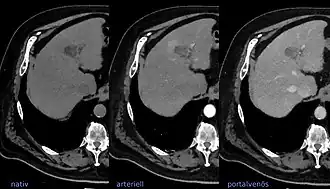

LIRADS classification is applied to multi-phase contrast-enhanced CT or MRI scans in people with certain chronic liver diseases. | |

The Liver Imaging Reporting and Data System (aka LI-RADS) is a quality assurance tool created and trademarked by the American College of Radiology in 2011 to standardize the reporting and data collection of CT and MR imaging patients at risk for hepatocellular carcinoma (HCC), or primary cancer of the liver cells.[1] It provides a standardized framework for classification of liver lesions by a radiologist, and only applies in patients with chronic liver disease, the main risk factor for liver cancer. The hierarchical classification, from LR1 to LR5, is based on specific imaging features of the lesion in question, and corresponds to the degree of suspicion for malignancy. For example, a lesion with features corresponding to the highest category, LR5, is "definitely" HCC. Importantly, the increasing acceptance of the LI-RADS system of reporting by referring clinicians (chiefly oncologists, hepatobiliary and liver transplant surgeons) has reduced the need for tissue biopsy confirmation of cancer in patients with chronic liver disease.